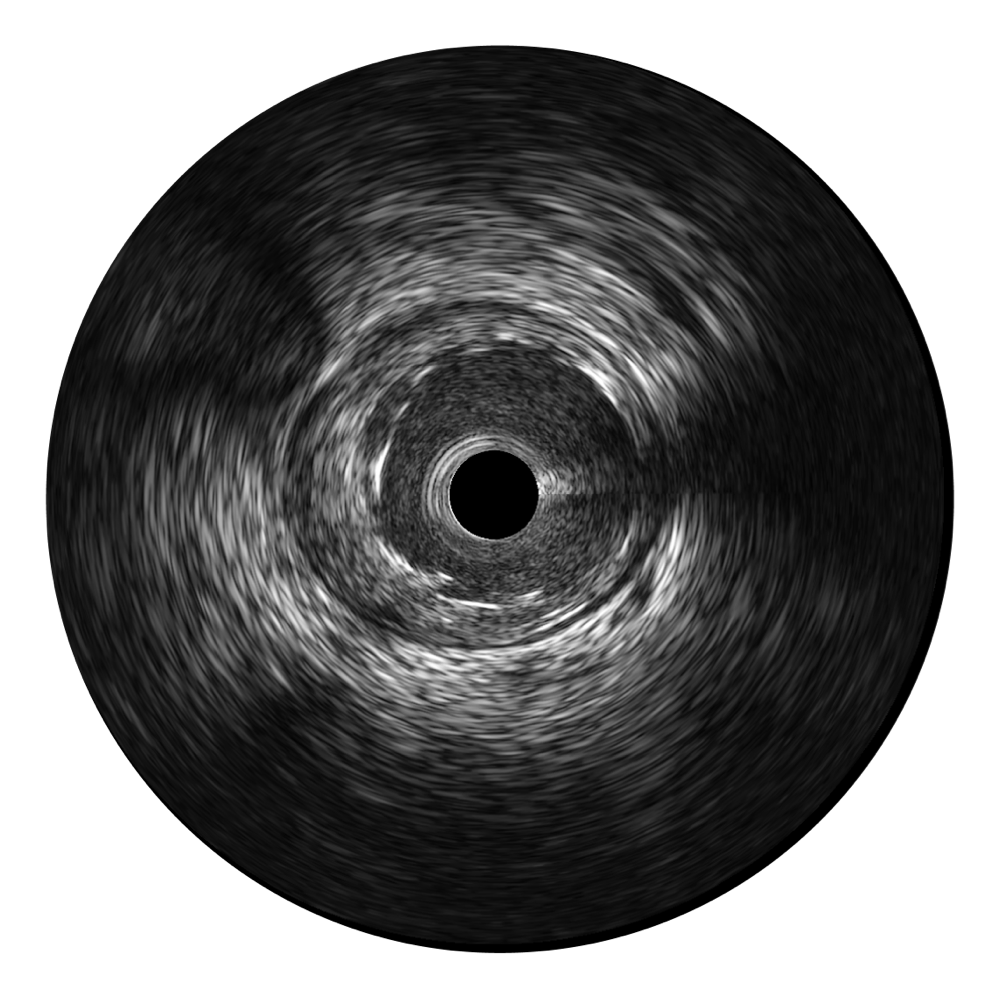

• milan米兰宽频IVUS图像

对比传统IVUS导管成像,milan米兰宽频IVUS图像的近场支架梁显影更细腻,远场中膜外血管仍清晰可辨,兼顾远中近,兼顾分辨力与穿透深度